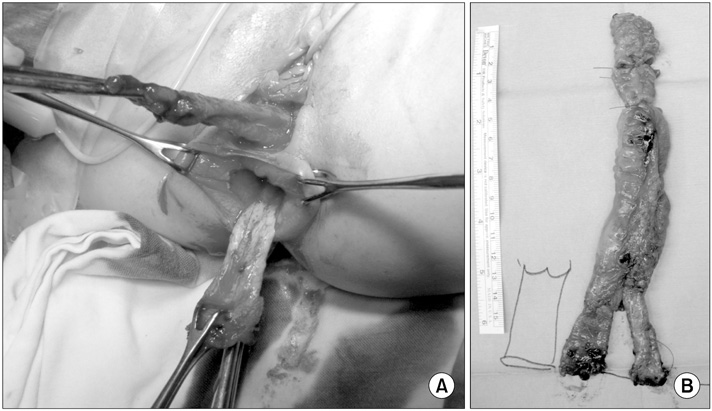

A 2-month-old female infant presented to our hospital with a 1-month history of stool passing through the vagina. She was born at 36 weeks' gestation weighing 1.875 kg and was the second infant of a twin. She had a ventricular septal defect that closed spontaneously at 1 month of age. Initially, she was diagnosed with a rectovaginal fistula. Despite conservative therapy, including a sitz bath, for 5 months, there was no improvement in her symptoms, and most of the stool still appeared to pass through the vagina. A colon study indicated a rectovaginal fistula directly connected to the distal rectum (

Fig. 1). Under general anesthesia, a small opening located posterior to and near the vagina at vestibule was found. The structure that had been misdiagnosed as a fistula based on the colon study was not present. The patient had a normally sited anus, an anterior ectopic anus, and a double vagina (

Fig. 1A preoperative colon study appeared to show that the contrast had passed to the vagina through a rectovaginal fistula (arrows).